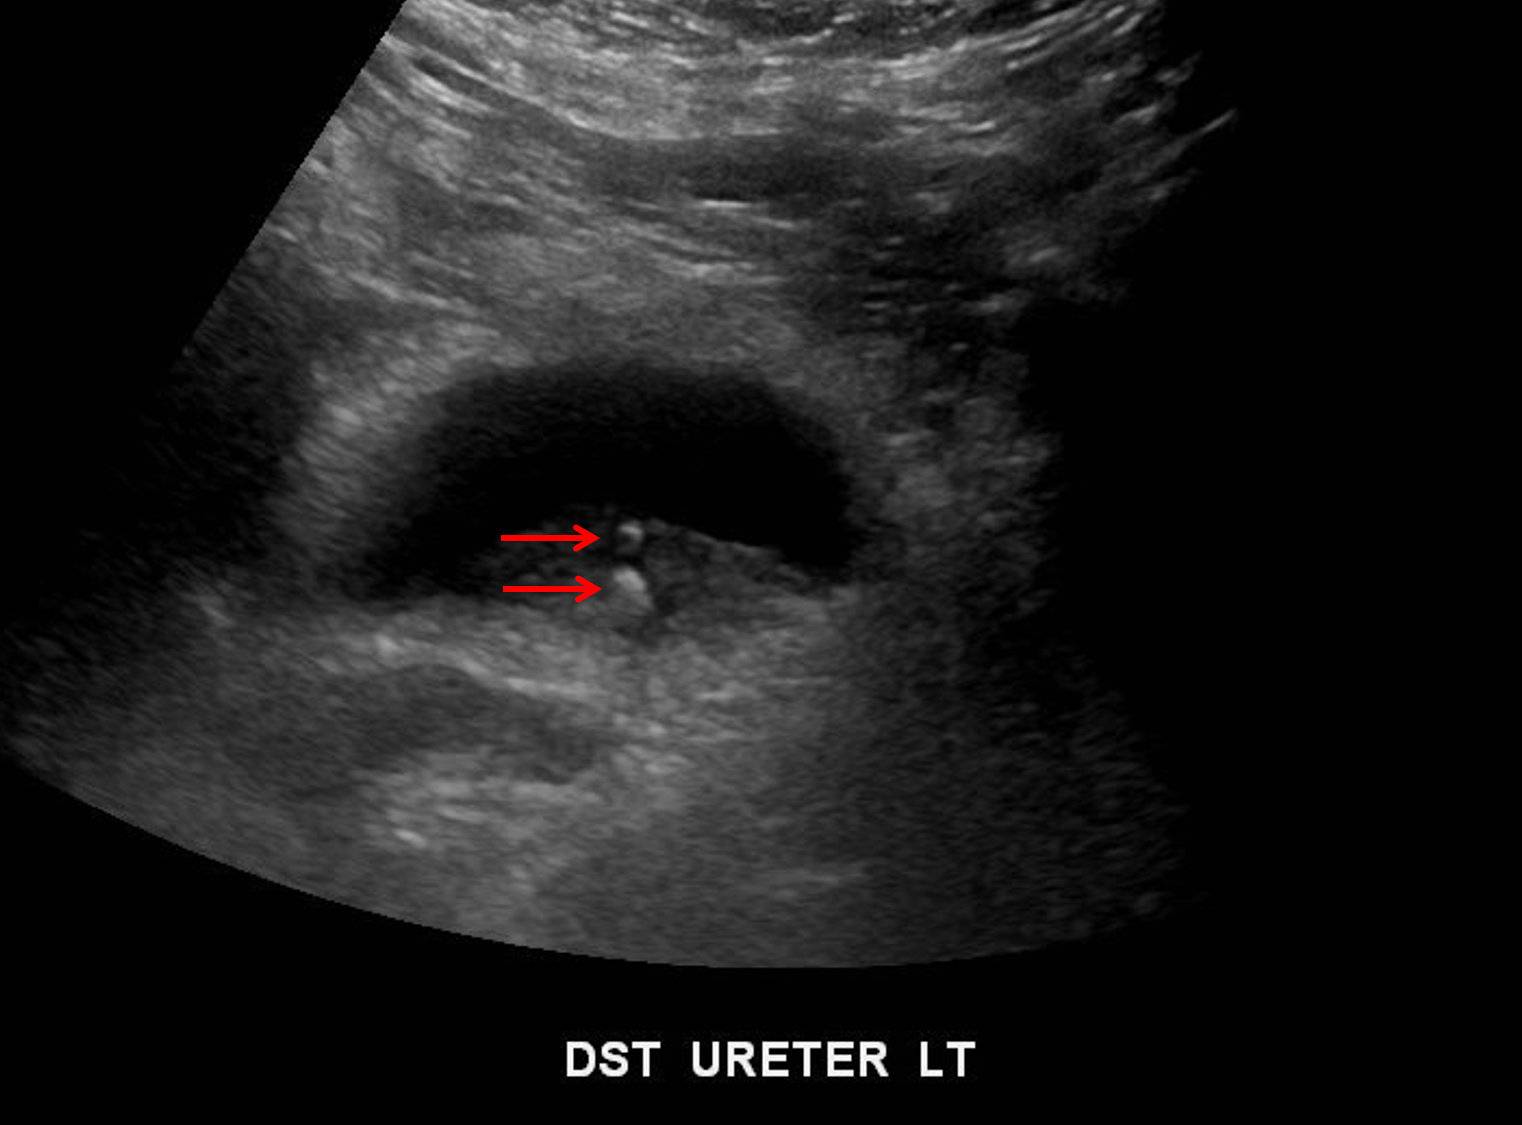

Sample ReportMultiple echogenic foci concerning for calculi in the distal left ureter, which measure up to 4 mm.

No definite hydronephrosis, though assessment is limited by posterior acoustic shadowing from bilateral medullary nephrocalcinosis. This also limits assessment of the bilateral nephrostomy tubes.

Bilateral renal cortical thinning.